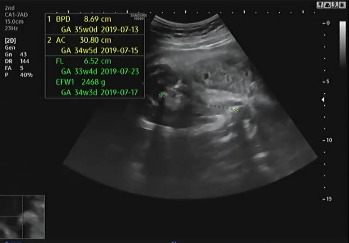

진료 순서가 되어 복부 초음파를 확인하였다. 여전히 햇님이는 자신의 건강함을 알리기 위해 초음파를 보는 내내 손을 이리저리 움직였다. 머리둘레, 복부둘레, 허벅지 뼈 길이를 측정하여 대략적인 체중을 확인하고 태아가 주수에 알맞게 크고 있는지를 확인했다. 머리둘레는 35주 차, 복부둘레는 34주 5일, 허벅지 뼈 길이는 33주 4일이라서 이상하다 생각했는데 평균적 수치는 주수에 알맞게 성장이라는 것을 듣고 안심했다. 2주 뒤인 37주 차에 내원을 예약했다.